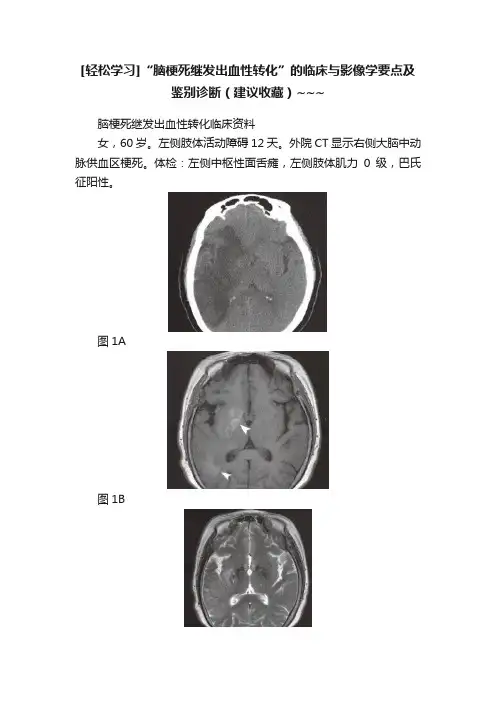

脑梗死继发出血性转化临床资料 女,60岁。左侧肢体活动障碍12天。外院CT显示右侧大脑中动脉供血区梗死。体检:左侧中枢性面舌瘫,左侧肢体肌力0级,巴氏征阳性。

图1A 图1B 图1C 图1D 图2 图3 影像学报告描述 轴位CT平扫(图1 A),右侧额叶后部、岛叶、基底核、颞叶大片扇形不均匀低密度灶,CT值18~23HU,边缘清楚,右侧侧脑室及外侧裂变窄,中线结构略左移。轴位T1WI(图1B),上述病变脑回肿胀及脑沟变窄,右基底核、右侧颞叶后部斑片状高信号(无尾箭头)。轴位T2WI(图1C),病变呈稍高信号,基底核区少许低信号。TOF MRA(图1D),右侧大脑中动脉M1段闭塞,右颞叶区域斑片状短T1信号(无尾箭头)。 影像诊断与最后诊断 均为:右侧大脑中动脉供血区大面积梗死继发出血性转化。 临床与影像学要点 出血性转化(hemorrhagic transformation,HT)是急性脑梗死的重要并发症,尤多见于栓塞性脑梗死。影像学报道HT发生率为20%~43%,尸解发现率高达71%。HT发生机制尚不明确,缺血持续时间越长,即缺血后再通时间越长,血管及其基底膜、血管外基质(extracellular matrix,ECM)破坏越明显,BBB完整性受损严重,出血的可能性也就越大。动物实验表明,缺血超过3小时及使用rtPA治疗者HT发生率很高。病理学上HT可为斑点状出血,也可以是大块出血灶。临床上大部分无症状变化,但仍有近1/4病例出现病情加重。 CT与MRI均可检出HT,但MRI更敏感。①CT平扫表现为低密度灶内斑点状、结节状或块状高密度影,CT值50~90HU,边缘欠清楚。如图2,左侧额顶叶梗死内HT呈局限性高密度(无尾箭头)。随访出血逐渐吸收或进展。②MRI典型表现为T1WI高信号与T2WI高信号,但急性期(<3天)出血需行T2*WI或SWI检查,表现为低信号。如图3(与图1同一例),SWI显示左侧颞枕叶脑梗死HT,呈斑片状低信号(无尾箭头)。③大块出血的密度与信号演变与自发性脑内血肿一致。④增强T1WI、 DWI、PWI及陈旧性出血对HT具有一定的预测作用,如明显强化、ADC值明显下降、脑灌注参数重度下降均提示HT可能性增大。 欧洲急性中风合作研究(ECASS)根据CT检查所见的低密度梗死灶内出现高密度改变范围将HT分类如下:HI1,梗死灶周边部点状出血;HI2,梗死灶内融合性点状出血,但没有占位效应;PH1,出血较多,占梗死面积少于30%,有轻度占位效应;PH2,出血超过梗死面积30%,有明显占位效应。其中HI1与HI2合称为HI,即出血性脑梗死(hemorrhagic infraction,HI),PH1与PH2合称为PH,即脑实质出血(parenchymal hemotoma,PH)。 鉴别诊断 包括其他表现为短T1信号的病变。①脑梗死后皮质层状坏死:发生于皮质区,可呈脑回状,CT一般密度不增高。②自发性脑内血肿:常位于基底核、丘脑部位或有血管畸形及动脉瘤征象。③肿瘤继发出血:有原发肿瘤病史,随访病变进展,增强扫描可见异常强化。 小结 HT是脑梗死常见的并发症,随着SWI等技术的普及,HT的发现率越来越高,但多无相应临床症状。HT典型影像学表现为CT高密度及MRI上出血信号。